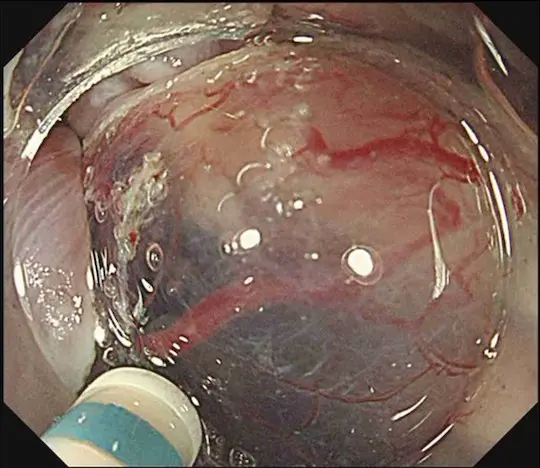

病変の下に生理食塩水を注射して浮かせた後、電気メスでマークの少し外側を切開します。

病変の下の組織を電気メスで剥がしていきます。

病変の切除を完了しました。白い矢印の内側が切除部位です。キズが出来ますが、時間の経過とともに自然に治って閉じます。